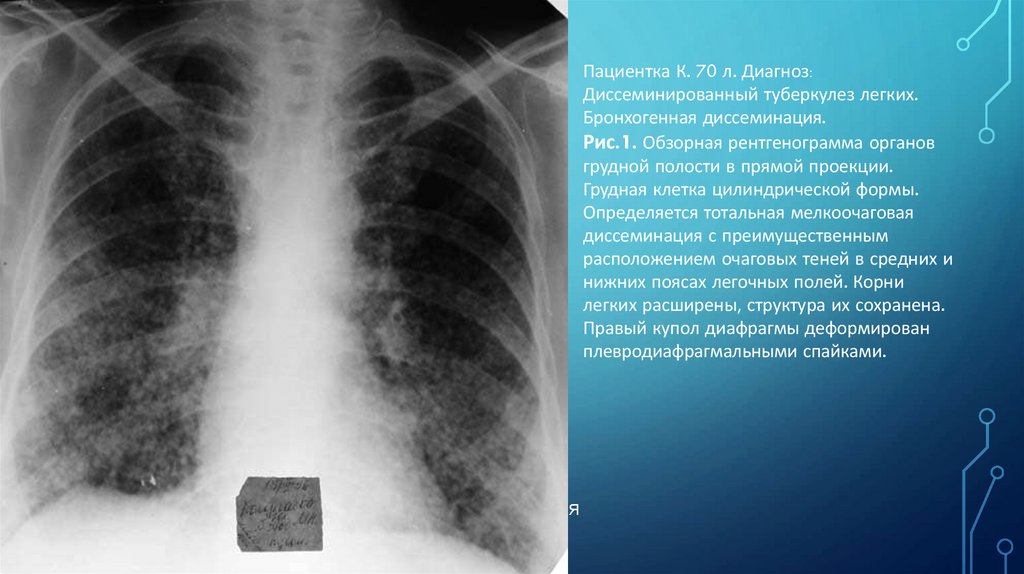

Пациентка К. 70 л. Диагноз:

Диссеминированный туберкулез легких.

Бронхогенная диссеминация.

Рис.1. Обзорная рентгенограмма органов

грудной полости в прямой проекции.

Грудная клетка цилиндрической формы.

Определяется тотальная мелкоочаговая

диссеминация с преимущественным

расположением очаговых теней в средних и

нижних поясах легочных полей. Корни

легких расширены, структура их сохранена.

Правый купол диафрагмы деформирован

плевродиафрагмальными спайками.

Н.С. ВОРОТЫНЦЕВА. С.С. ГОЛЬЕВ РЕНТГЕНОПУЛЬМОНОЛОГИЯ